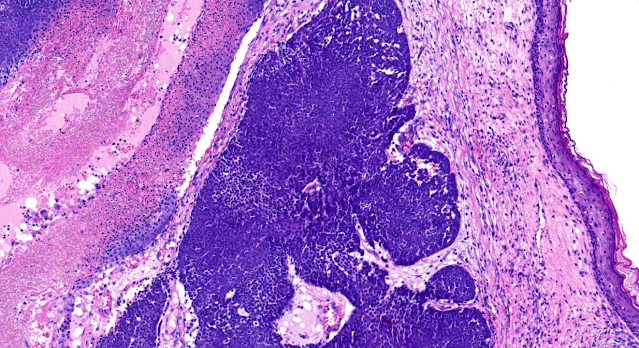

Dermatopathology Case 252 Get link Facebook X Pinterest Email Other Apps July 30, 2022 A 30 year old woman. Lesion on the forehead. Answer Get link Facebook X Pinterest Email Other Apps Comments